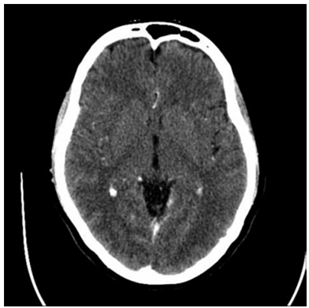

A tomografia computadorizada de crânio com contraste

encontra-se a seguir.

(https://radiopaedia.org/. Disponível em: https://prod-images-static.radiopaedia.org/images/4169564/65a780977632d0e771466c905c2195_gallery.jpg)